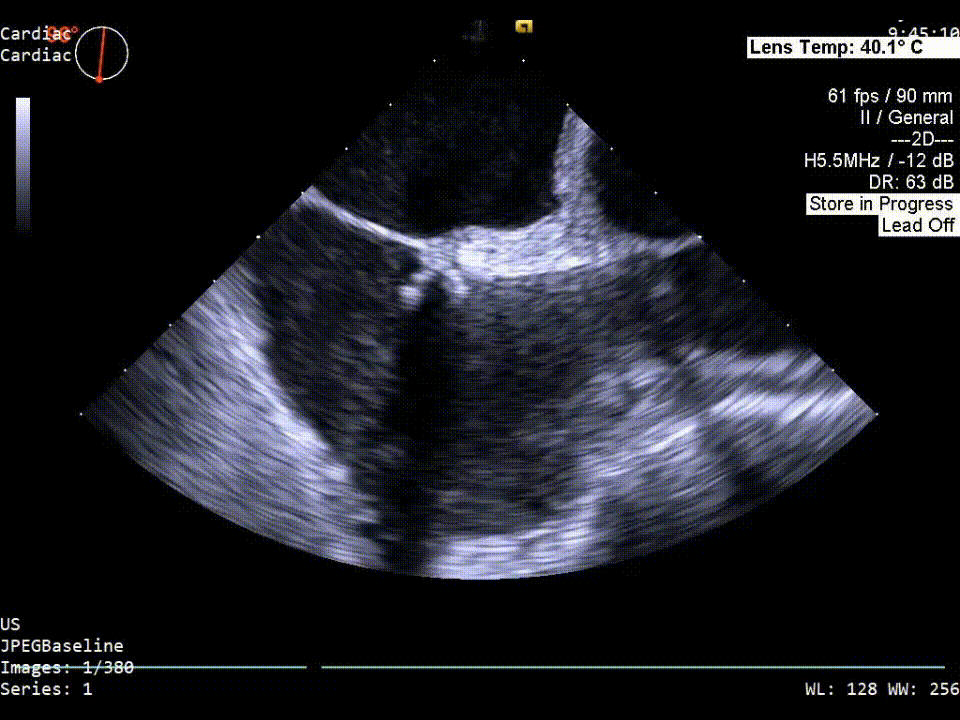

原发隔缝合器沿左上肺静脉导丝穿过PFO进入左房后打开开合臂对原发隔组织进行捕获扣合。待确认为最佳位置后操作手柄对原发隔组织进行穿刺缝合。

原发隔缝合超声影像

拉紧缝合线后进行发泡实验,超声显示卵圆孔闭合效果良好,无气泡分流,可进行锁结。

拉紧缝合线后发泡实验超声影像

完成锁结后进行发泡实验,超声显示:术后卵圆孔闭合效果良好,无可见气泡分流。

完成锁结后发泡实验超声影像